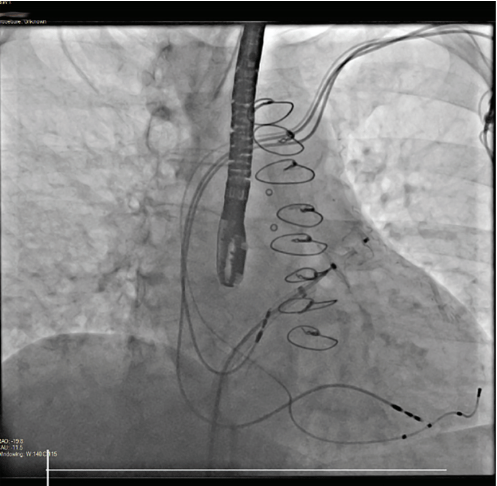

A 78-year-old woman was referred to Northside Hospital Heart Institute for possible LAAC. She had a history of coronary artery bypass grafting (CABG) over 5 years ago, permanent AF with history of atrioventricular node ablation, and permanent pacemaker implantation. Her CHA2DS2-VASc score was 5 due to hypertension, age >75, diabetes, and vascular disease. This placed her at high risk for stroke, but her cardiologist deemed her not to be a good candidate for long-term oral anticoagulation due to intracranial hemorrhage with multiple falls. An operative report of the CABG was obtained, but the report showed only 3-vessel bypass with no report of LAA ligation. Computed tomography (CT) with contrast of the heart was also obtained, which is standard practice for many of our LAAC procedures, especially for patients who have had prior cardiac surgeries. There was a 5.3-mm leak noted at the surgical closure at the base of the LAA (Figure 1). This leak was too large to close with endovascular coils, and there was concern about using an endovascular plug due to length of the leak and possible effects of radial forces over time in the channel. The Amplatzer Amulet device was chosen for this case, with the plan to place the lobe inside the LAA and place the disc covering the channel with forces after closure to be axial in direction. The procedure was performed under general anesthesia and transesophageal echocardiography (TEE) imaging. LAAC procedures at Northside Hospital Heart Institute are usually performed using TEE guidance only, with no use of contrast, since our noninvasive physicians (Drs John Ricketts and Colin O’Brian) provide imaging for transseptal puncture, device deployment, and post-imaging for any leaks, including 3D TEE at every step when needed. Due to the unusual nature of this anatomy, we performed contrast fluoroscopy of the LAA. Figures 2A and 2B show the pre-implant and periprocedural TEE images. Figure 3 shows the contrast injection through the 12 French Torque Vue 45-degree Amulet delivery sheath (Abbott) and the Glidewire (Terumo Interventional Systems) in the LAA. The placement was primarily guided by TEE imaging. The smallest size (16 mm) Amulet device was chosen for closure. Figure 4 demonstrates placement under fluoroscopy. Figures 5A and 5B demonstrate closure using TEE imaging. Post procedure, the patient was placed on aspirin and clopidogrel for 3 months. Once adequate seal is confirmed at 3 months, the goal is for the patient to switch to aspirin (81 mg).